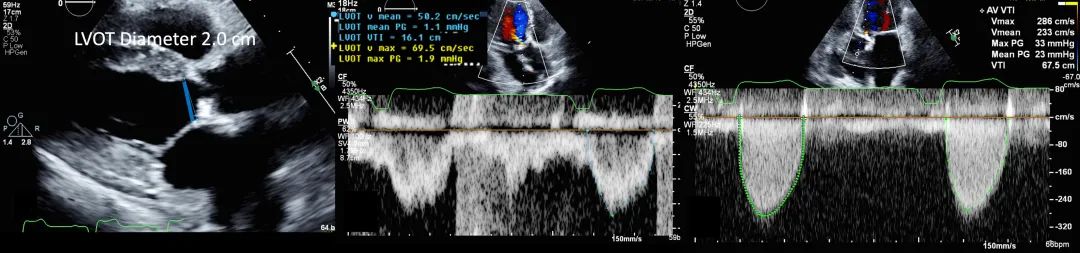

14、使用连续性方程(continuity equation)计算主动脉瓣瓣口面积(图15):所需参数包括胸骨旁长轴切面测量的左室流出道(LVOT)直径(步骤3),左室流出道流速或流速时间积分(步骤9和/或步骤12),以及主动脉瓣流速或流速时间积分(步骤8、11和13)。窦性心律时取3个测量值的平均值;心房颤动时取5个测量值的平均值。需强调的是,应在所有可能的声窗位置测量主动脉瓣峰值流速。

图15. 使用连续性方程计算主动脉瓣瓣口面积

主动脉瓣瓣口面积通过连续性方程计算,其所需参数包括从胸骨旁长轴切面测得左室流出道直径,以及LVOT流速和主动脉瓣流速。

3、胸骨旁长轴切面:测量左室流出道(left ventricular outflow tract,LVOT)直径(于心脏收缩中期测量)、主动脉窦直径、主动脉瓣瓣环直径、窦管交界直径和升主动脉直径(图4)。

图4. 左室流出道和主动脉根部测量

胸骨旁长轴切面测量左室流出道直径(收缩中期测量;左图,蓝线)、主动脉瓣环直径(右图,绿线)、主动脉窦直径(右图,红线)、窦管交界直径(右图,黄线)和升主动脉直径(右图,白线)。缩写同图2。